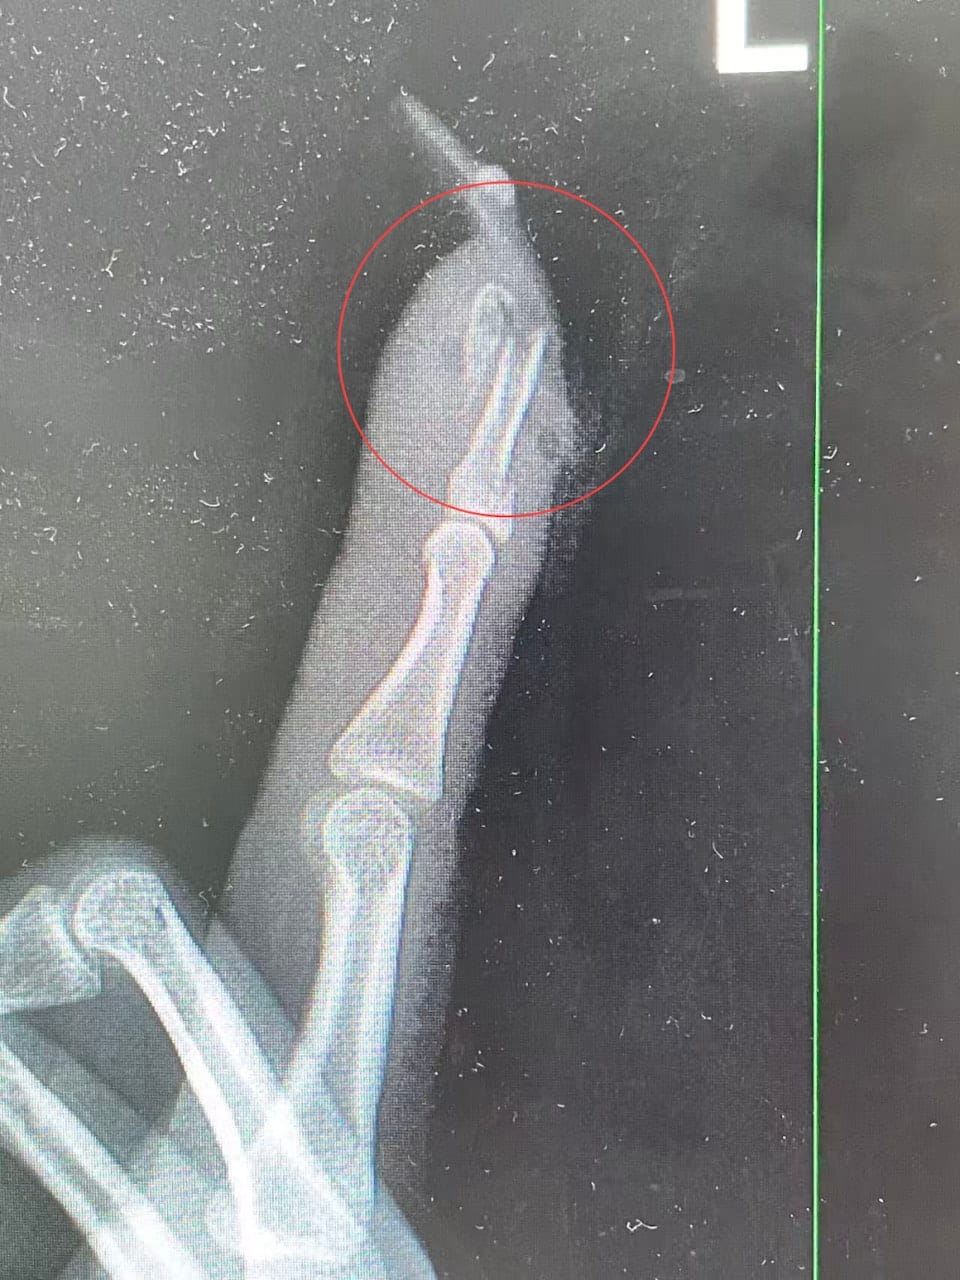

经检查发现,王女左手食指出现指骨骨折、甲床破裂,部分甲床外露,必须通过手术修复。院方为她进行指骨骨折闭合复位内固定手术,目前术后恢复情况良好。